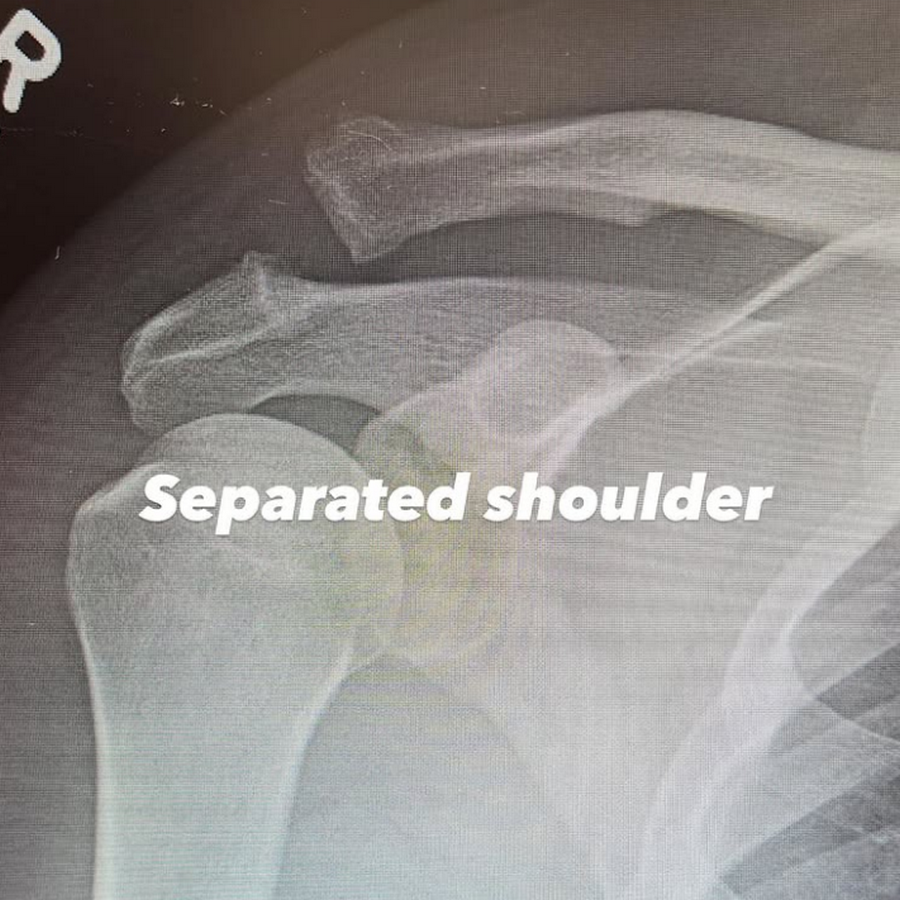

Пізніше у сторіз Ченнінг опублікував два фото, одне підписане як «вивих плеча», а під іншим — «прикручене плече», з зображенням східчастого гвинта, вкрученого в його плече.